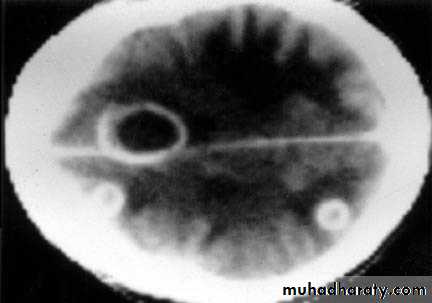

Brain Abscess CT without contrast

Brain Abscess CT with contrast